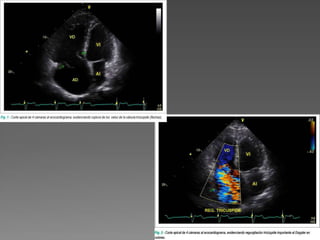

 Paciente del sexo masculino, con 57 años, víctima de trauma torácico,

causado por arma blanca, ocurrido hace 19 años, se remitió a

evaluación cardiológica con diagnóstico de hipertensión arterial. En la

ocasión del trauma torácico, se sometió a drenaje de hemotórax,

hemopericardio y corrección quirúrgica de la laceración miocárdica.

 Actualmente, el paciente viene presentando disnea a los grandes

esfuerzos, incomodidad abdominal y edema de miembros inferiores.

Al examen físico, se presentaba en buen estado general, eupnéico y

con presión arterial (PA) de 140/90 mmHg. Al examen del pulso

venoso yugular, se observó ingurgitamiento yugular con evidente

onda v. La ausculta cardiaca reveló soplo sistólico más audible en el

borde esternal izquierdo inferior, acentuado con la inspiración.

 El electrocardiograma demostró bloqueo completo de la rama

derecha. En la radiografía de tórax, se observó aumento del índice

cardiotorácico, pero sin evidencias de congestión pulmonar.